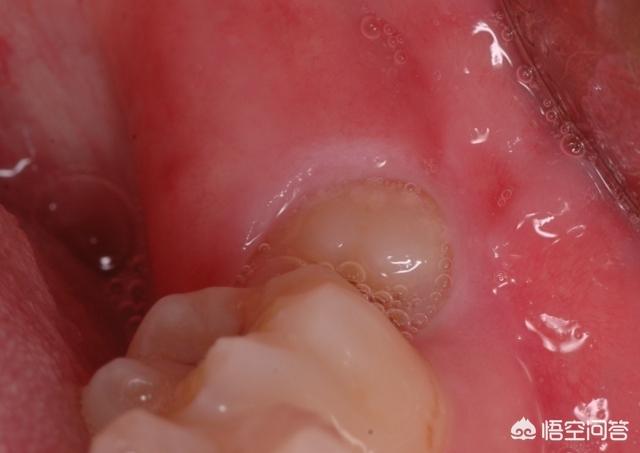

智齿发炎疼痛怎么办 头条问答

智齿发炎疼痛怎么办 及时吃药打针 疼痛难忍需拔掉 黑六网

头条问答 牙龈发炎能不能拔智齿 8个回答